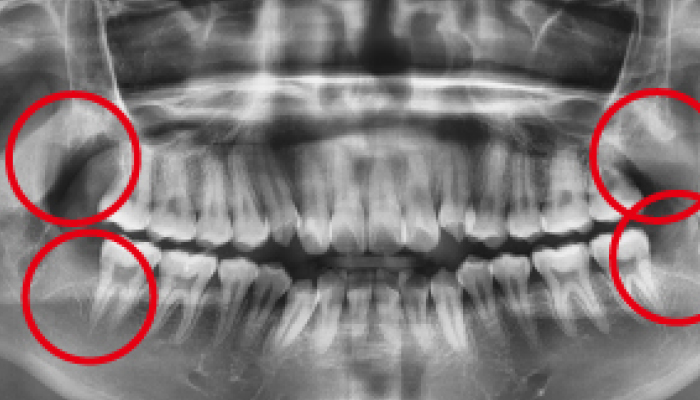

사랑니 발치 전후 사례

• 치료 전

치료 후